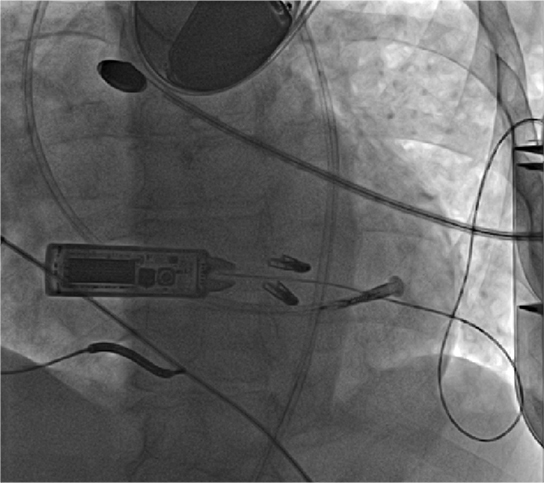

WiSE™ CRT System wirelessly transmits ultrasound energy to a receiver electrode implanted inside the left ventricle. (Courtesy of Weill Cornell Electrophysiology)

The WiSE-CRT System (wireless simulation of the endocardium) consists of a receiver electrode and an ultrasound transmitter. The tiny wireless electrode about the size of a grain of rice is implanted directly inside the left ventricle and stimulated by an ultrasound transducer implanted underneath the skin in the left chest. Participating patients will have either an existing pacemaker or defibrillator that paces the right side of the heart. The transducer will detect that stimulation from the right side of the heart and then send an ultrasound beam to the electrode, which is sitting in the left side of the heart. Resynchronization is achieved within a fraction of a second without the use of pacing leads. This approach also provides cardiologists with a greater choice of pacing locations, thereby enabling patient-specific customization of the pacing site